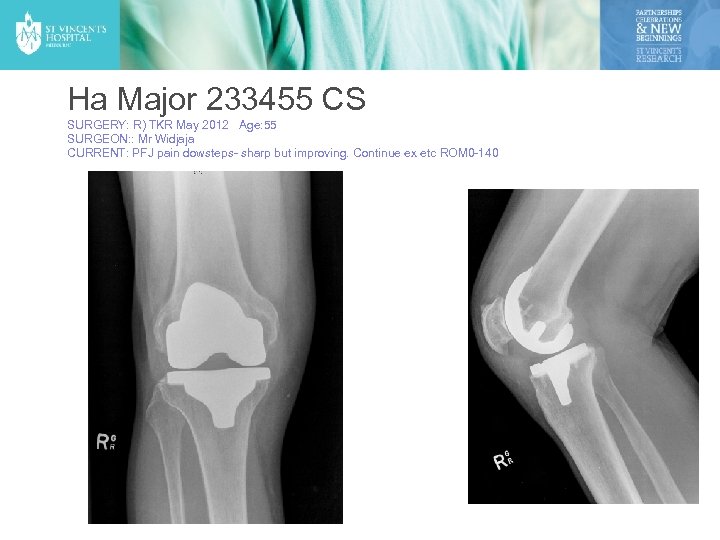

Ha Major 233455 CS SURGERY: R) TKR May 2012 Age: 55 SURGEON: : Mr Widjaja CURRENT: PFJ pain dowsteps- sharp but improving. Continue ex etc ROM 0 -140